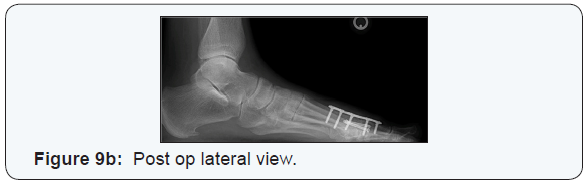

Patient’s were placed non-weight bearing for five days and then allowed to begin ambulation as tolerated, in a controlled ankle motion walker with a Plastazote®ray cut out. Radiographs were taken at 4, 8 and 16-week intervals until fusion was determined by the operating surgeon (Figures 9a-9b).

There was a 97.4% union rate in spite of early weight bearing. Of the thirty-eight patients in the study, 34.2% (13/38) patients had complete union radiography at 8 weeks and 63.2% (24/38) patients showed union at 12 weeks. The construct proved to be stable and was able to resist the effects of early weight bearing with radiographic union rates and average time frame to fusion of 10.6 weeks. Study limitations include the retrospective nature of the study, and the fact that the operating surgeon was involved in determining radiographic fusion using post operative radiographs. The use of CT scanning might be a better determinant of actual fusion across the joint.